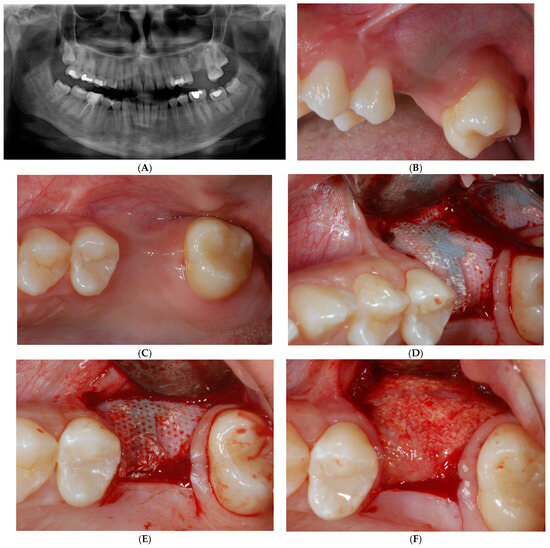

A 22-year-old healthy, non-smoker female patient presented with a chief complaint of recurrent infections of the first maxillary left molar due to a large osteolytic lesion caused by the failure of repeated endodontic therapies, as revealed by computed tomography (CT) scans (Figure 1A,B).

Computed tomography (CT) scans revealed large osteolytic lesion of first maxillary left molar caused by failure of repeated endodontic therapies (A). Cross-sections showing buccal bone loss (B).

Treatment options were discussed, and the patient signed a consent form for the tooth extraction and the subsequent augmentation procedure, to be scheduled as a staged approach for implant site development. Four months after the tooth extraction, soft tissue healing reached a proper maturation (Figure 2A,B), and a new CT was requested to evaluate the wound healing and bone availability for implant therapy. The CT scans revealed a horizontal ridge defect (Figure 2C,D–F) that required correction with a staged GBR procedure.

Soft tissue healing four months after tooth extraction (A,B). New CT was requested to evaluate wound healing and current bone availability for implant therapy. CT scans revealed horizontal ridge defect (C–F) that had to be corrected with a regenerative procedure.